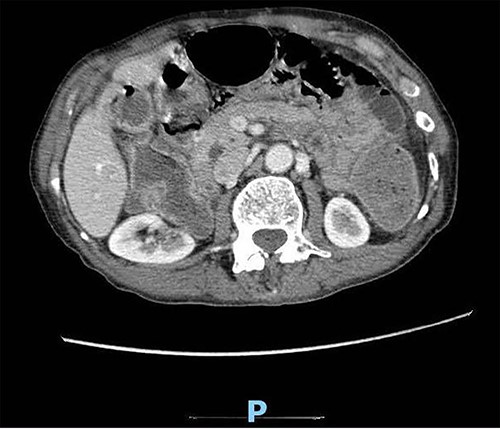

A 89-year-old male patient was admitted to the emergency department complaining of generalized abdominal pain for 4 days. The pain was associated with repeated vomiting and obstipation. He also reported a history of chronic constipation. However, he denied any history of melena, hematochezia, weight loss, night sweats or fever. His past medical history revealed a history of prostatic cancer and pulmonary fibrosis caused by tuberculosis. The patient was diagnosed with symptomatic gallstones two years prior to his presentation, after undergoing an enhanced CT scan of the abdomen (Fig. 1) for abdominal pain. Although he was offered cholecystectomy, he refused the surgery due to his high-risk medical condition.

Enhanced CT scan of the abdomen confirming the presence of a 2.5-cm gallstone.